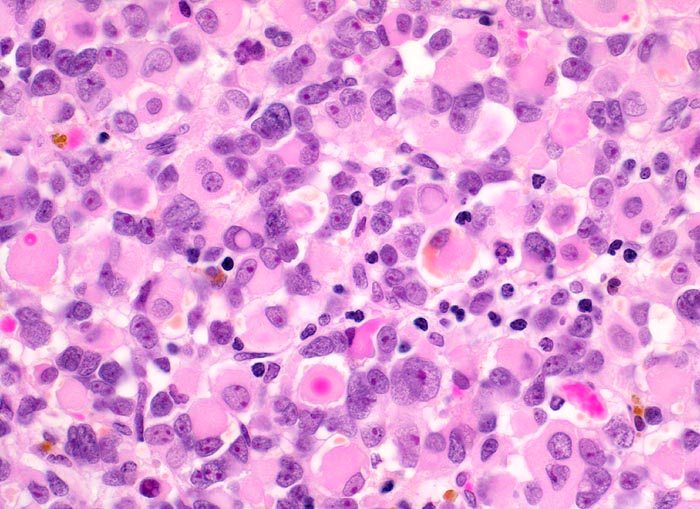

Das makroskopische Bild ist uncharakteristisch und variiert in Abhängigkeit von der Lokalisation. Fokale Nekrosen und zystische Degeneration sind häufig. Es werden verschiedene histologische Subtypen unterschieden, welche charakteristische molekulargenetische Aberrationen aufweisen und mit unterschiedlichen Prognosen assoziiert sind. Die beste Prognose haben botryoide und spindelzellige Rhabdomyosarkome gefolgt von embryonalen Rhabdomyosarkomen (intermediäre Prognose) und alveolären bzw. pleomorphen Rhabdomyosarkomen (schlechteste Prognose). Therapieantwort und Prognose hängen neben der Histologie auch von der Lokalisation ab. Embryonale Rhabdomyosarkome zeigen ein breites morphologisches Spektrum. Dieses reicht von wenig differenzierten Tumoren, die nur mittels Immunhistochemie und Elektronenmikroskopie diagnostizierbar sind zu gut differenzierten Tumoren, die fetaler Muskulatur ähneln. Oft findet sich eine Mischung von wenig differenzierten kleinen, runden und/oder spindeligen Zellen und eine variable Anzahl differenzierter Rhabdomyoblasten mit reichlich eosinophilem Zytoplasma. Die Rhabdomyoblasten können rund, spindelig, kaulquappenförmig oder spinnwebenförmig sein. Besser differenzierte Zellen enthalten reichlich Zytoplasma mit Querstreifung, welche allerdings teilweise nur elektronenmikroskopisch nachweisbar ist.

• Konjunktivalschleimhautfragment. Fibrinauflagerungen anstelle der langstreckig abgeschilferten konjunktivalen Zylinderepithelbedeckung (unten).

• Chronisches lymphoplasmazelluläres Entzündungsinfiltrat im subepithelialen Stroma mit unscharfer Begrenzung zu einem zellreichen soliden Tumor.

• Dieser besteht aus mesenchymalen Zellen mit unterschiedlicher Ausdifferenzierung.

• Die am wenigsten ausdifferenzierten Zellen zeigen wenig amphophiles Zytoplasma und ovale Kerne.

• Dominierend sind in diesem Tumor teils mehrkernige Rhabdomyoblasten mit reichlich eosinophilem Zytoplasma und exzentrischem Zellkern. Die Querstreifung des Zytoplasmas ist in der HE Färbung nur andeutungsweise erkennbar.

• "Spinnwebenzellen" mit peripheren Zytoplasmavakuolen.